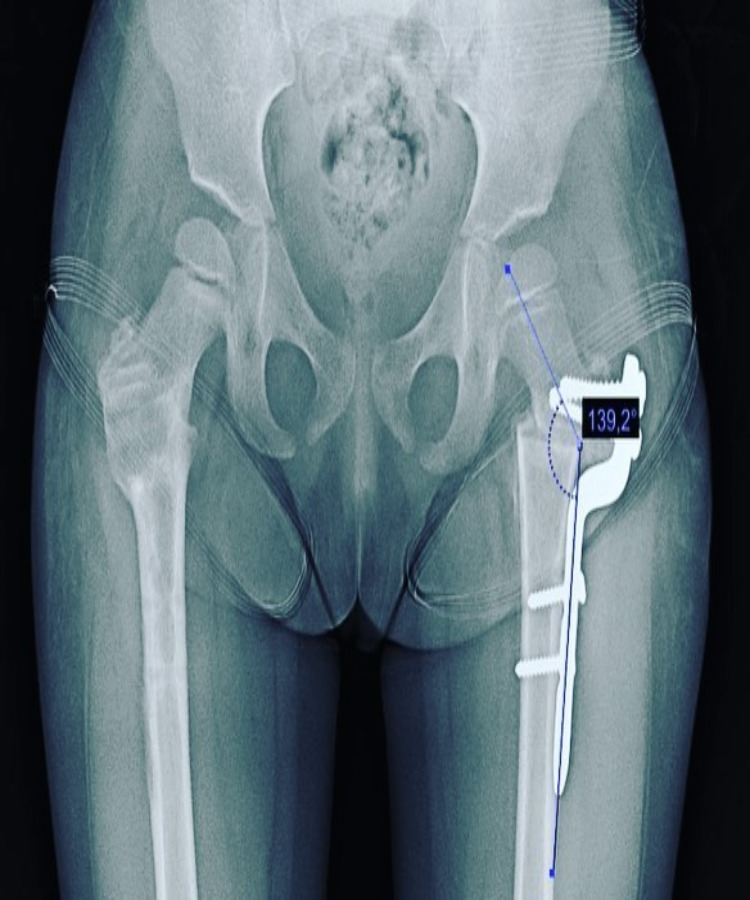

Técnicas quirúrgicas pediátricas restauran función y apariencia de extremidades con lesiones graves o deformidades congénitas, buscando mejorar funcionalidad y estética.

Las deformidades de pie y rodilla incluyen genu varo, genu valgo, pie plano y pie cavo, con causas congénitas o postraumáticas.